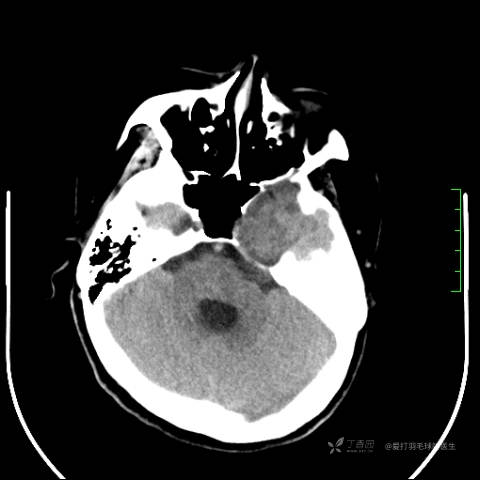

中年女性,全身多处“疙瘩”,长了切,切了又长,分型是关键,已公布结果。

患者性别:女

患者年龄:44岁

主诉:患者因反复右侧腰痛伴右下肢麻木2年余入院。

简要病史:自诉右甲状腺功能亢进症多年,规律服药,平素多有心悸、胸闷、活动后明显。既往腰椎椎管内肿瘤切除术。